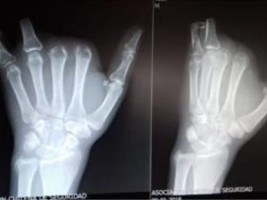

L’accident s’est produit le 16 novembre dernier à Los Angeles, dans la région de Nuñble, plus précisément dans les locaux de la société Serfocom spécialisée dans les services forestiers et la construction. Dominique Melvin affirme que l’entreprise ne lui aurait pas donné les instructions nécessaires pour faire fonctionner en toute sécurité un convoyeur qui l’a amputé dans l’accident de quatre doigts.